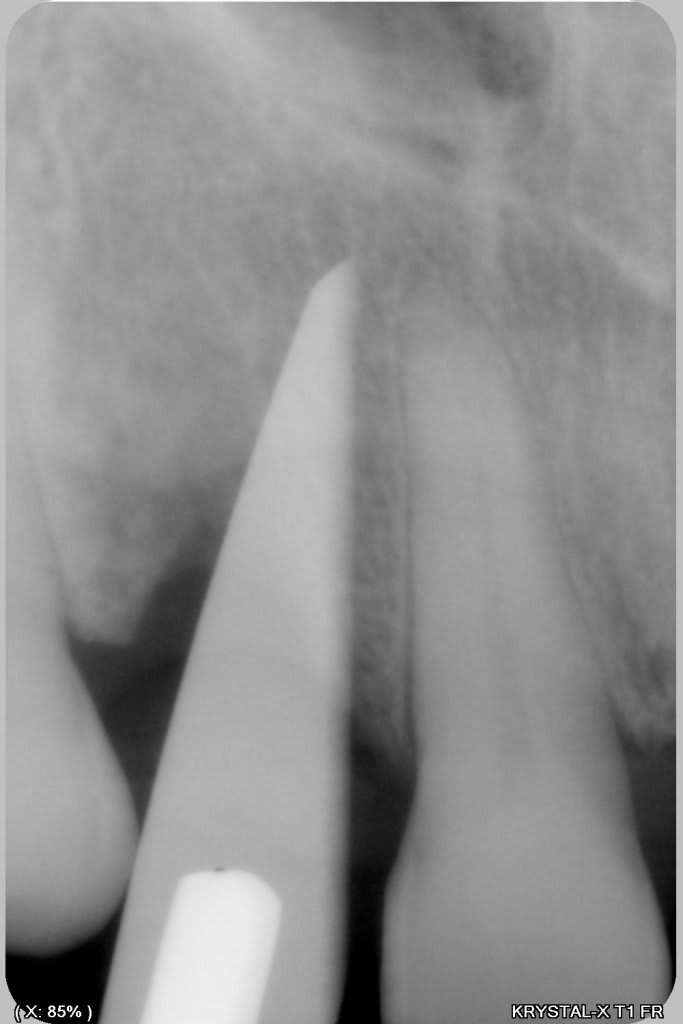

un petit cas comme j'aime, perte de 11, avec atteinte de la paroi vestibulaire.

Manipulation de la paroi palatine, afin de déplacer la moitié de l'os en vestibulaire, et pose d'un Px (Anthogyr) utilisation, de lame 11, ostéotome demi lune de Tatum, spreader (Meissinger) et divers.

de mémoire un PX 34100 ou 34120